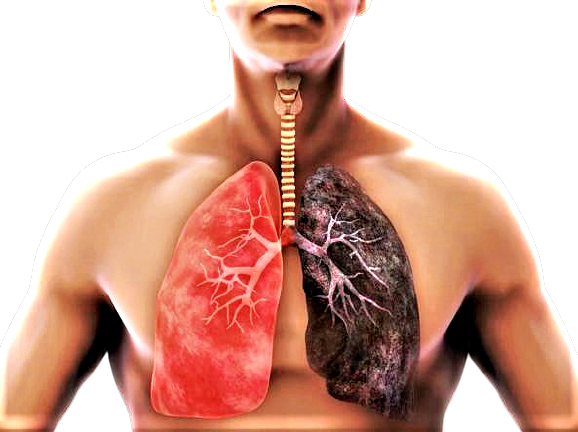

Fumo e tumore al polmone, rischio malattia non è uguale per tutti

Lo studio bioMILD è stato condotto su circa 4.000 persone, arruolate all`inizio del 2013. Il 70% dei partecipanti era costituito da forti fumatori – cioè consumatori in media di un pacchetto di sigarette al giorno (20 sigarette) per 30 anni – con un`età superiore ai 55 anni, il restante 30% comprendeva volontari nella fascia d`età 50-55 anni, fumatori di 30 sigarette al giorno, sempre da almeno 30 anni. Tutti sono stati sottoposti alla combinazione LDCT-test miRNA, quest`ultimo eseguito attraverso il semplice prelievo di un campione di sangue. I miRNA sono piccolissime molecole, molto specifiche, che vengono rilasciate precocemente dall`organo aggredito dalla malattia e dal sistema immunitario. Il test miRNA è stato scoperto e sviluppato presso l`Istituto Nazionale dei Tumori ed è la prima volta che un test molecolare sul sangue si rivela efficace nello screening, predicendo il rischio di malattia. Proprio grazie a questo test sarà possibile in futuro definire un programma di prevenzione personalizzata e integrata con la diagnosi precoce.

“La nostra ipotesi di partenza era che il rischio di ammalarsi per i forti fumatori non fosse omogeneo, cioè il medesimo per tutti” – spiega Ugo Pastorino, Direttore della Struttura Complessa di Chirurgia Toracica di INT e tra gli autori dello studio. “I risultati ci hanno dato ragione perché sulla base degli esiti della TAC e del test miRNA siamo stati in grado per la prima volta di profilare il rischio di malattia e di definire che, a parità di esposizione, il rischio biologico è diverso”. I risultati sono stati significativi: il 58% dei partecipanti è risultato negativo a entrambi i controlli ed è stato classificato a rischio basso di tumore del polmone, mentre il 37% è risultato positivo a uno dei due esami (rischio medio) e il restante 5% ha avuto entrambi i valori positivi con un rischio molto più alto di ammalarsi.

“I vantaggi che otteniamo sono diversi” – continua Pastorino – “innanzitutto, in base alla fascia di rischio viene messo a punto un programma di prevenzione personalizzato, che parte naturalmente dalla disassuefazione dal fumo. Inoltre, è possibile ridurre il numero di TAC di controllo, dal momento che chi è a rischio basso viene rivisto a distanza di tre anni. Infine, ultimo ma non meno importante, è possibile stabilire chi non necessita di cure immediate ma solo di un controllo annuale, e questo ci permette di evitare interventi che sarebbero inutili, a tutto vantaggio del paziente”. Il primo passo è quindi smettere di fumare: è stato infatti accertato che con la disassuefazione dal fumo si può ottenere una riduzione fino al 50% della mortalità per tumore del polmone.